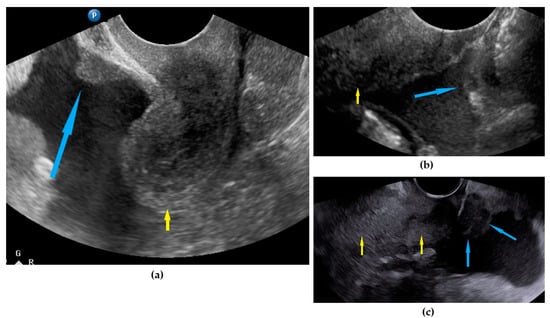

| Frozen pelvis | Massive pelvic involvement: hypoechogenic tissue in the peritoneum in the pouch of Douglas, forming cohesion between ovarian masses, bowel, uterus, and posterior pelvic wall. It manifests in the dynamic ultrasound examination: absence of sliding sign between the rectum and uterus/ovaries and between the uterus, urinary bladder, and pelvic walls. | Figure 12 | Video S12 |